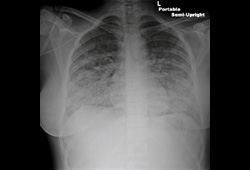

- radiografia torácica